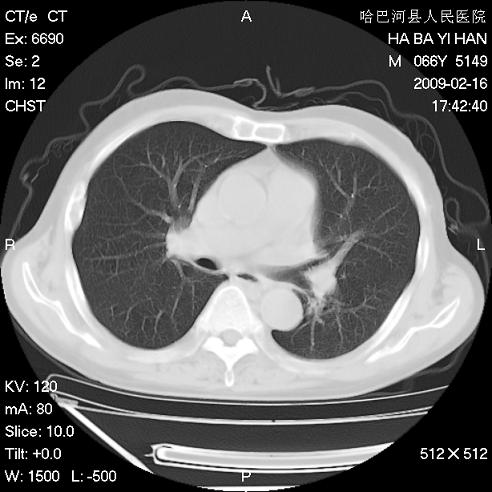

以下是引用huangxun4321在2009-2-16 20:18:00的发言:[br]部分病灶可见硬化边,部分可见骨质破坏消失,部分病灶内可见骨脊,说明病灶内既有良性病变,又有恶性病变,考虑骨巨细胞瘤恶变,未除骨纤恶变,畸形性骨炎少见,亦要考虑.

以下是引用731208在2009-2-16 20:31:00的发言:[br]考虑恶性胸膜间皮瘤并肋骨,脊柱转移。

以下是引用yijiansheng在2009-2-16 20:16:00的发言:[br]考虑恶性胸膜间皮瘤并肋骨,脊柱转移。

以下是引用形影不离在2009-2-16 19:55:00的发言:[br]考虑多发性转移瘤。